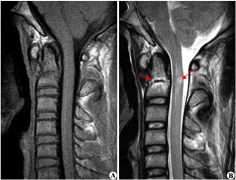

脊髓肿瘤 是儿童少见的病变。多数(90%)脊髓肿瘤为胶质肿瘤,其中大部分为恶性肿瘤。这些病变的少见还表现在全部中枢神经系统胶质瘤中,只有2-4%位于脊髓。较后,35%的椎管内肿...

问: 什么是脊髓肿瘤 ?MRI核磁影像如何解读瘤种? 答:脊髓肿瘤是位于椎管(神经通道)中的神经和神经周组织肿瘤。根据肿瘤与脊髓和硬脑膜(包裹神经的膜)之间的位置关系...

Q:脊髓肿瘤是良性还是恶性? A:脊髓肿瘤指发生于脊髓本身、以及椎管内与脊髓邻近的肿瘤。 按肿瘤与脊髓关系,由内向外可以分为三类:脊髓髓内肿瘤,脊髓髓外硬脊膜下肿瘤,硬...